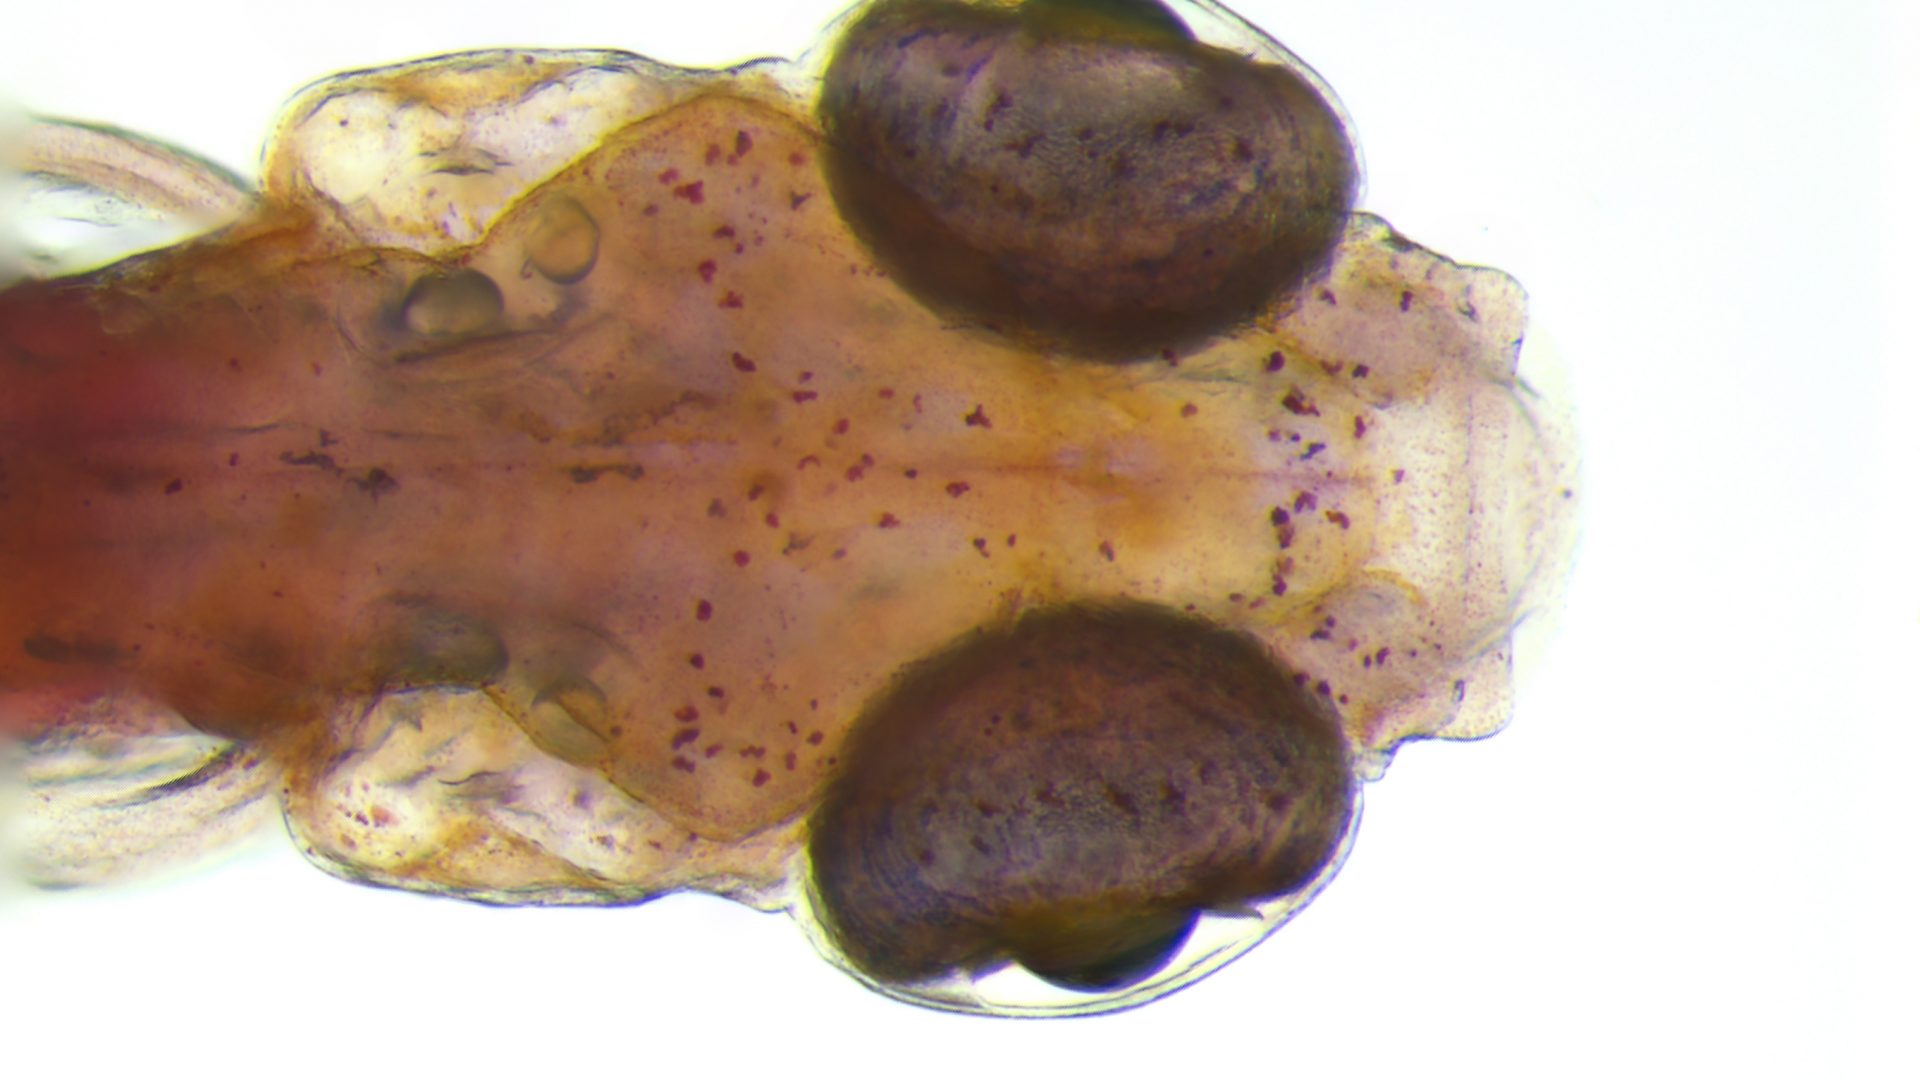

Dit is de kop van een zebravislarve. In die vroege levensfase is het visje doorzichtig. Voor wetenschappers is die eigenschap bijzonder waardevol: met een microscoop kunnen biologische processen – bijvoorbeeld in de hersenen – direct worden gevolgd in een levend visje. De informatie die daardoor wordt verkregen, is ook voor de mens van groot belang.

“Onderzoek aan zebravis-hersenen helpt onze kennis over het menselijk brein vooruit. Niet alleen het gezonde brein, ook bij hersenziekten”, vertelt dr. Tjakko van Ham van de afdeling Klinische Genetica. “De visjes zijn, als ze uit het eitje komen, doorzichtig. Daardoor kunnen we met behulp van een microscoop direct in de hersenen kijken, zonder de hersenen open te hoeven maken. Het visje kan gewoon blijven leven, zodat we het gedurende lange tijd kunnen onderzoeken.”